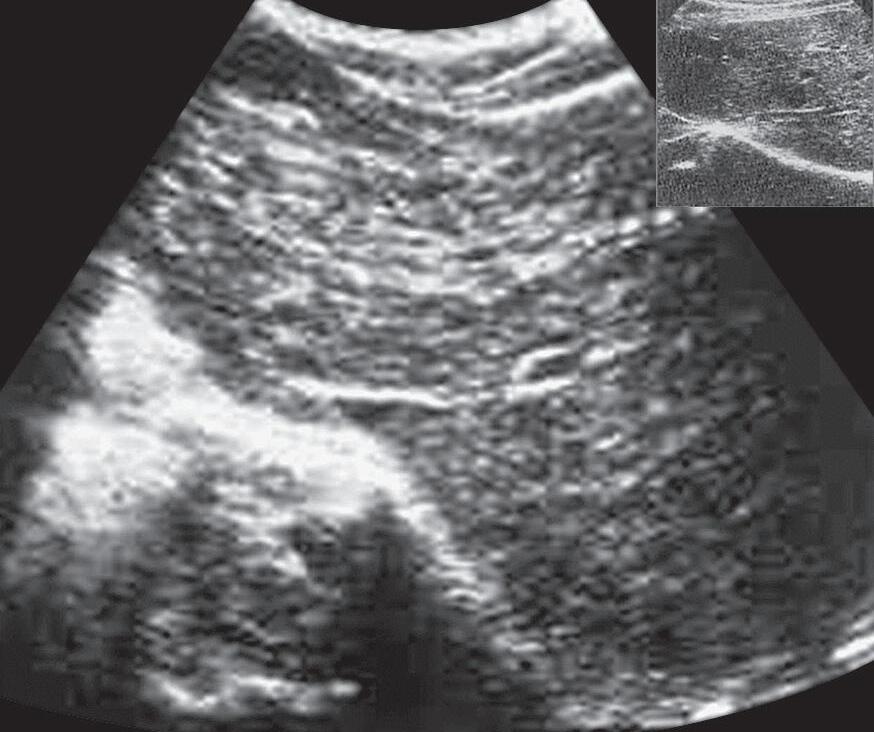

Fig. 15-8. (a) ultrassonografia (usG) de fígado cirrótico. (b,c) Correlação com a anatomia e a histologia.